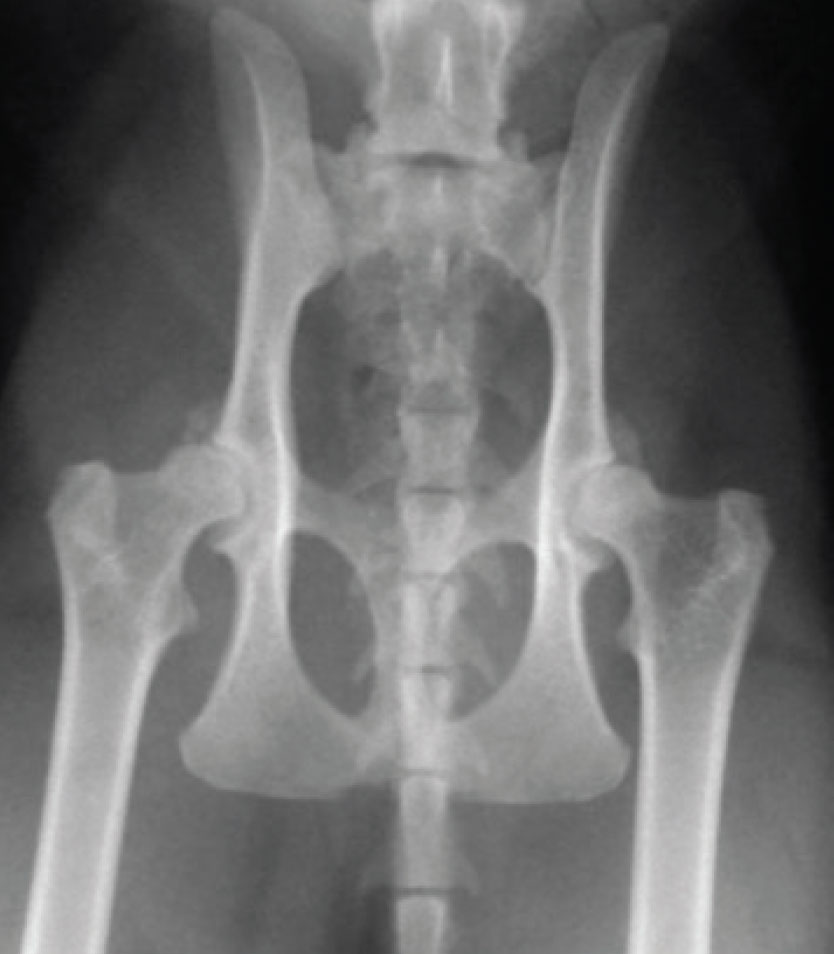

Degenerative joint disease refers to damage in both the appendicular and axial skeletal systems, with most of the cases diagnosed as osteoarthritis. OA implies a joint problem, primarily associated with degeneration and loss of cartilage and proliferation of bone in the form of osteophytes around the joint. This results in a joint that has a reduced range of motion and one that is undergoing low grade inflammation resulting in varying degrees of pain and swelling of the offending joint(s). It is common in cats where multiple joints are impacted. In cats, OA usually occurs as a primary problem with no easily identifiable underlying cause, but it can also occur secondary to underlying developmental joint disease such as hip dysplasia (see Figure 2) or subsequent to a joint injury such as an intra-articular fracture or luxation. Cats develop osteoarthritis in all their large joints, but particularly the hip, hock and elbow joint3,4 (see Figure 3). Over 80% of cats older than 12 years of age had axial skeletal changes.4 Appendicular skeletal changes are even more common with over 90% of cats of all ages having radiographic changes in at least one joint.3

Figure 2. Hip osteoarthritis in an eight-year-old domestic short-haired cat secondary to hip dysplasia. Large bilateral osteophytes are present on the cranial acetabulum.